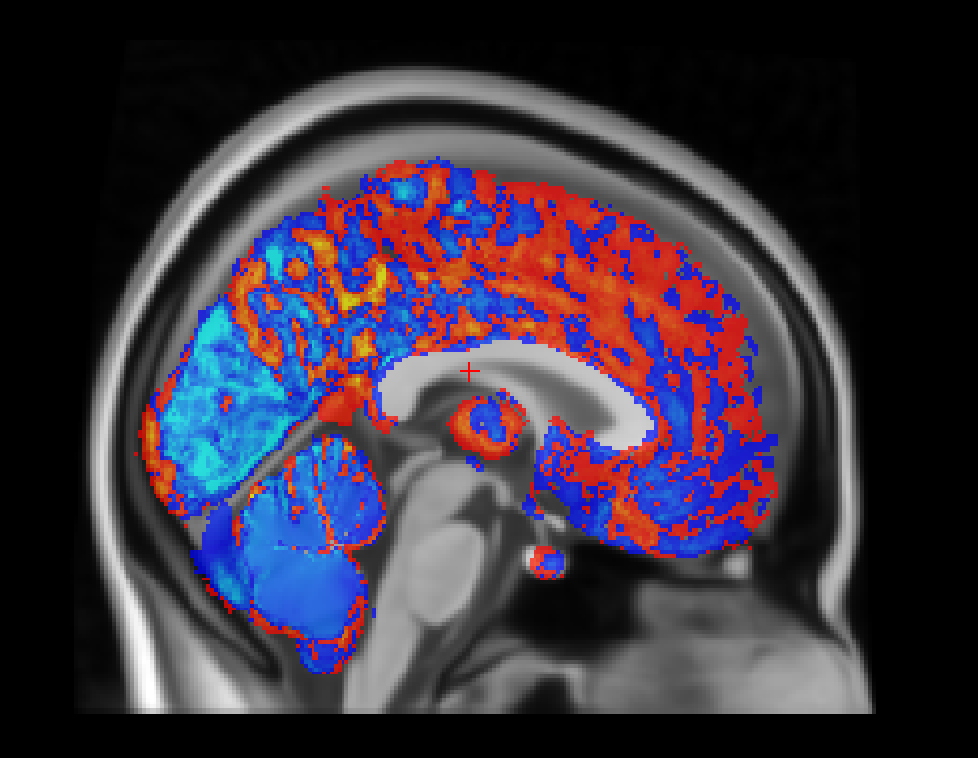

The group difference analysis provides visual output showing statistical comparisons between experimental groups:

Figure: group differences in electric field distributions